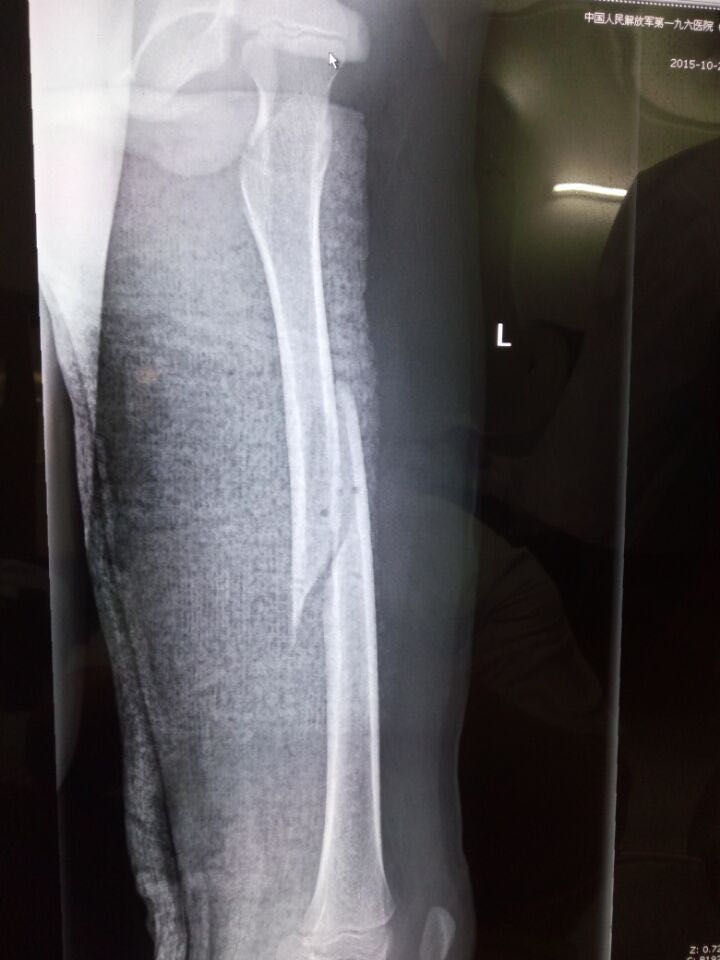

患者,3岁,图为其胫骨。大家觉得正常吗?

胫骨